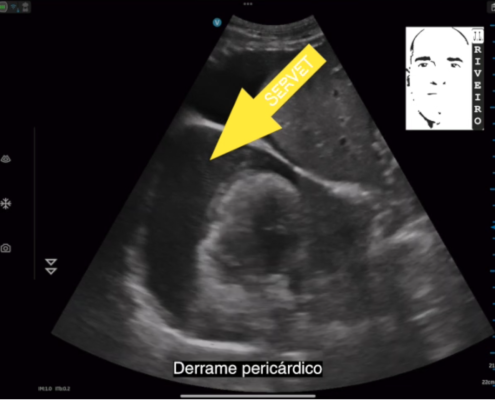

Servet, como Centro de Referencia, se mantiene al día de todas las novedades que afectan al desarrollo de nuestras actividades, con dos objetivos principales, mejorar la formación del personal clínico e incorporar los medios tecnológicos más avanzados. Esto nos permite mejorar el bienestar de los animales atendidos.